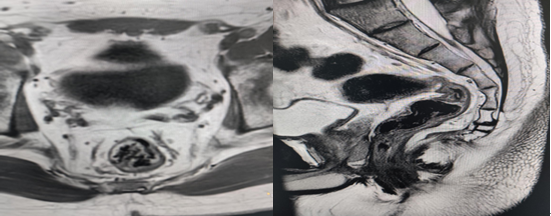

2.子宫及附件、前列腺、直肠等器官的疾病诊断及临床分期。

直肠磁共振高分辨成像